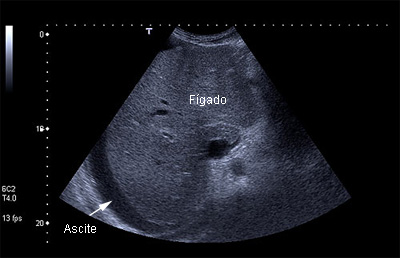

A ascite, quando pequena, não causa sintomas, sendo diagnosticada apenas por exames de imagem (principalmente a ecografia, que é realizada rotineiramente no cirrótico para rastreamento do carcinoma hepatocelular).

Para fins de classificação da cirrose na escala de Child-Pugh, a ascite é dividida entre “ausente”, “leve” e “moderada/severa”. A ascite leve englobaria a ascite observada apenas por exame de imagem (como a ultrassonografia) e a observada no exame físico, mas sem grande aumento do volume abdominal. A ascite moderada seria a que leva a aumento significativo no abdome, mas sem a presença de falta de ar (dispneia) e/ou de abdome tenso pela grande distensão, que seriam característicos da ascite severa.